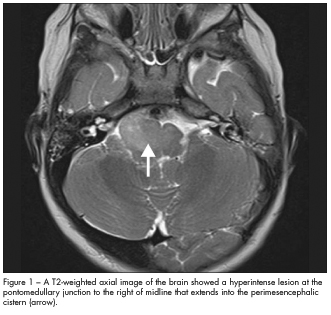

In this case, MRI scans of the brain revealed an infiltrative mass in the brain stem that involved the lower pons and medulla (Figures 1 and 2). This suggested a probable diagnosis of low-grade brain stem glioma. The child did not undergo brain biopsy for tissue diagnosis because of the critical location of the tumor. He was closely monitored by the neuro-oncology team. At follow-up 9 months later, an MRI scan showed the lesion to be stable; neurological findings were unchanged.